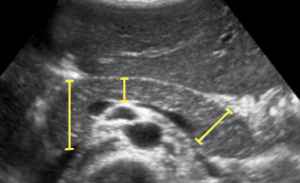

سونوگرافی رحم و تخمدان برای چیست؟ سونوگرافی رحم و تخمدان (Pelvic Ultrasound) برای اندازه گیری و ارزیابی ارگان هایی که در لگن وجود دارند، انجام می شود. در واقع سونوگرافی رحم و تخمدان درباره اندازه، موقعیت و ساختار توده های موجود در لگن، اطلاعات تشخیصی را به پزشک ارائه می دهد. در سونوگرافی رحم چه چیزهایی مشخص میشود؟ گفتیم که در سونوگرافی رحم و تخمدان، اندام های لگن زنان مورد ارزیابی قرار می گیرد. اما